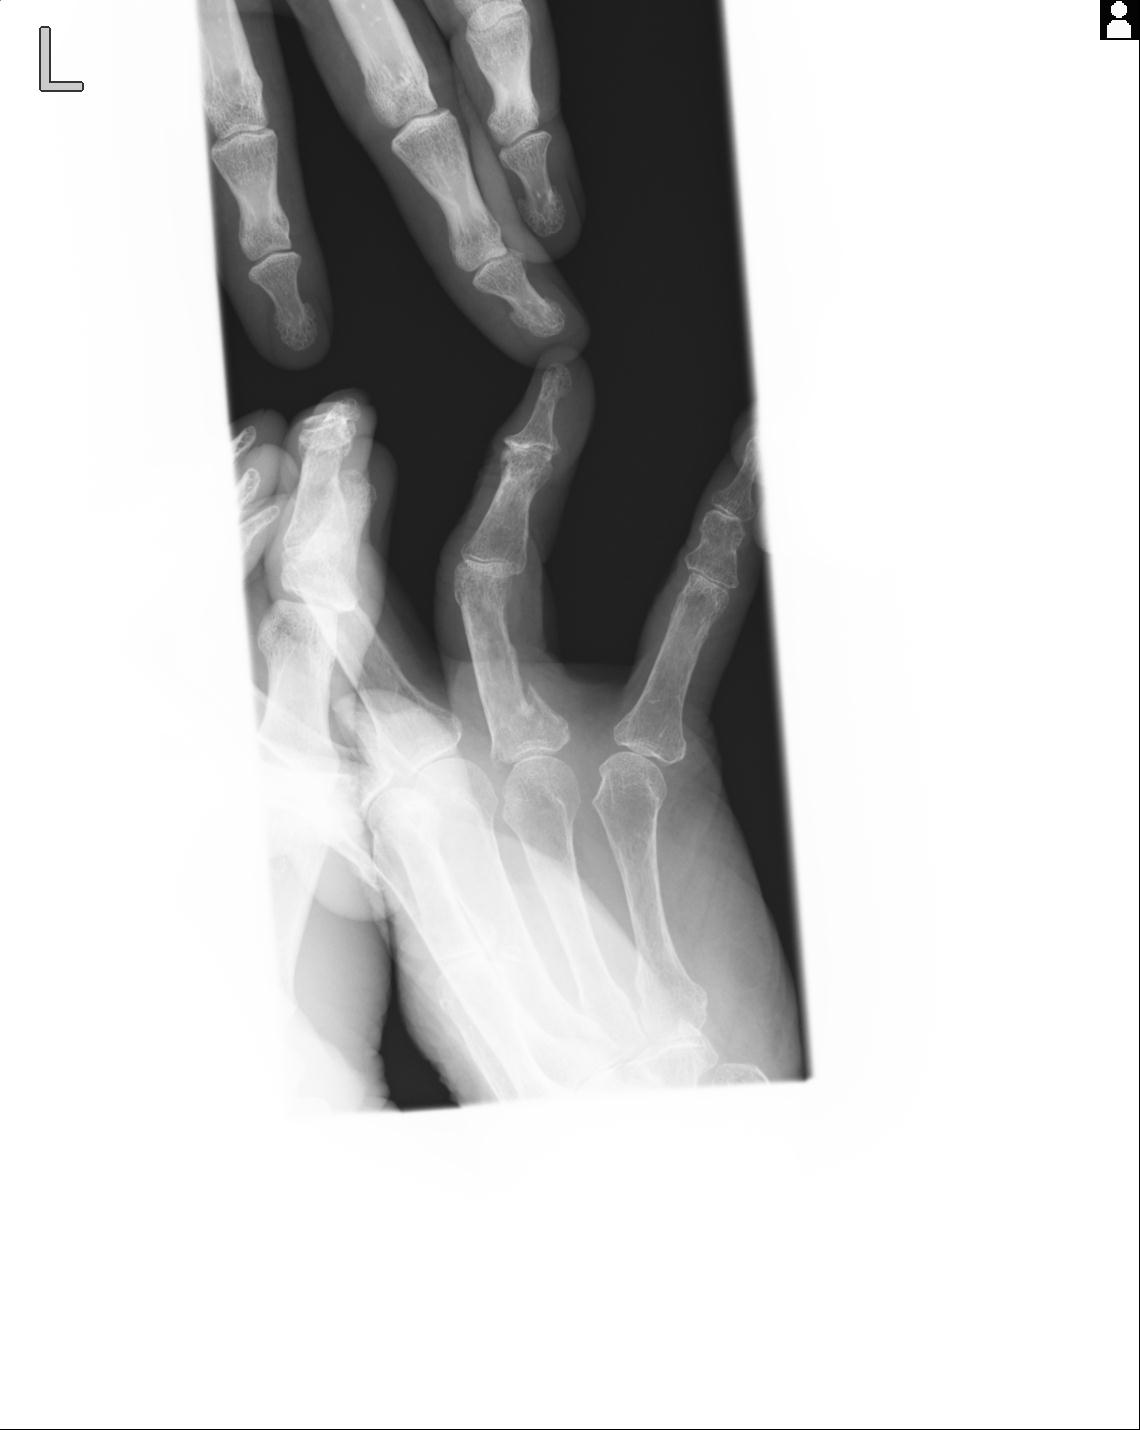

46666 1/23 両股正面+軸と右手関節 2R 76歳女性 右橈骨遠位端

102860 1/21 (4R) 1/26 (4R) 3/15 左手 2R 91歳女性 左環指中節骨

102766 1/5 1/12 左手関節 4R 28歳男性 左橈骨遠位端

50435 1/4 1/15 手関節 4R 17歳女性 右橈骨遠位端

102739 12/30 1/5 左手関節 4R 92歳女性 橈骨遠位端

101290 1/4 5/21 5/20 手関節 2R 17歳男性 橈骨遠位端